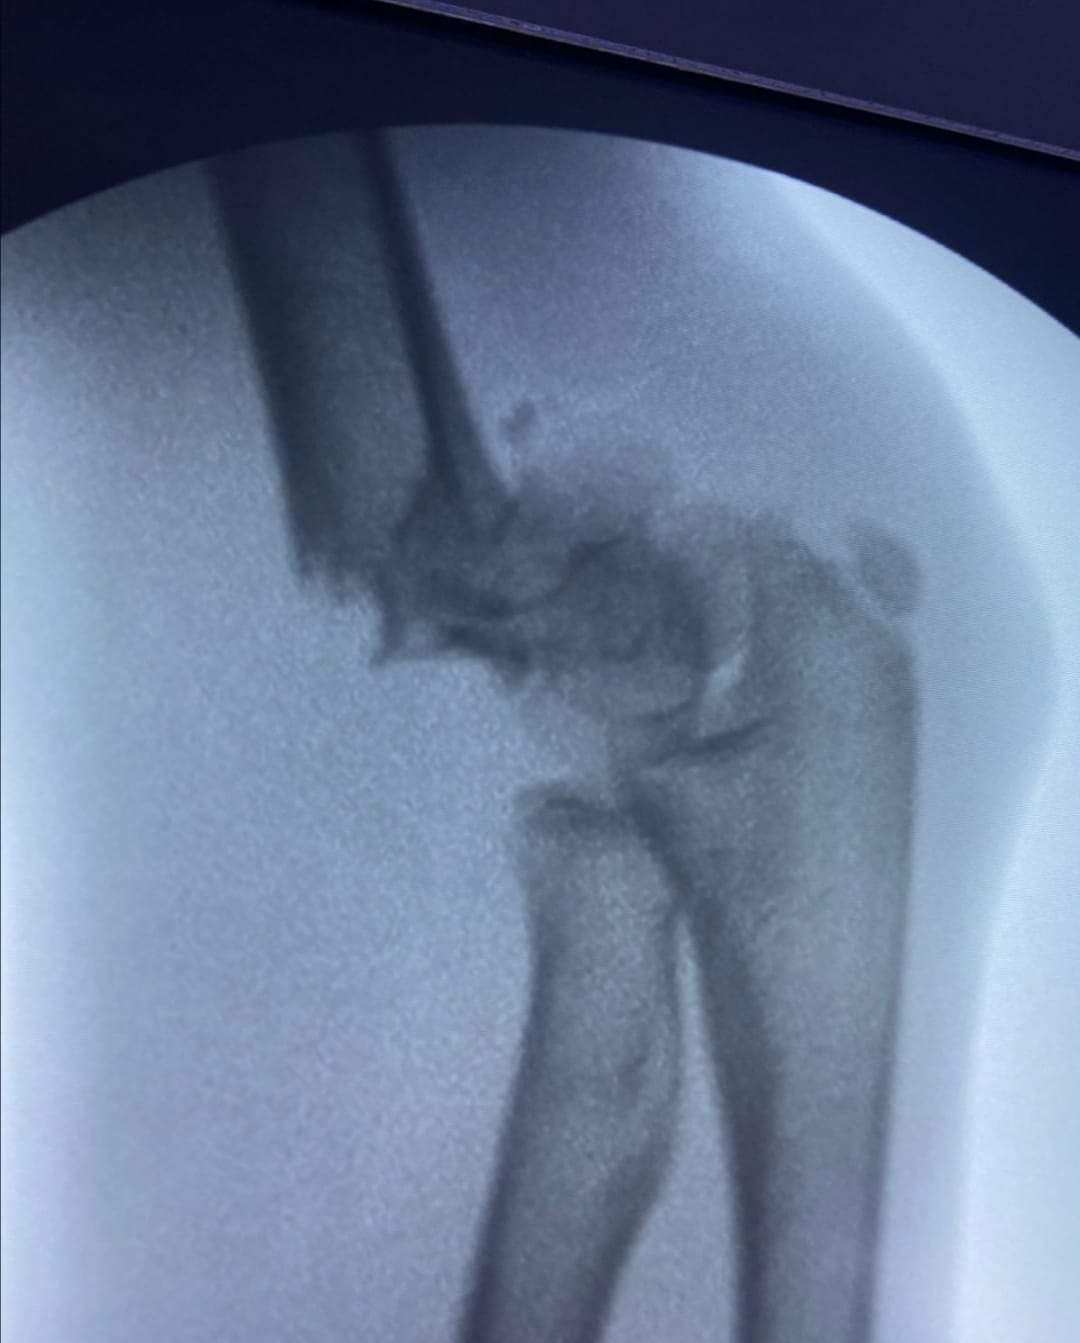

وطنا اليوم -  يقوم بعمليات تثبيت الكسور المعقدة بشكل طاريء وتبديل المفاصل بشكل مبرمج  مما خفف على المواطنين البحث عن أسرة في مستشفيات مركزية رغم صعوبة عمليات العظام من الناحية التقنية في المستشفيات النائية  إضافة الى  استقبال اعداد كبيرة بالعيادات ومعالجة جميع المرضى بالطرق المثلى انه الدكتور الانسان البارع والمتميز يزيد البريزات طبيب العظام في مستشفى الاميرة سلمى / ذيبان عيادة العظام  علماً بأنه كان  مستشفى تحويلي منذ تاسيسه والدكتور البربزات وقبل اربع سنوات في عام 2020  منذ انتقاله للمستشفى يقوم بهذه العمليات ومن بينها  عمليات نوعية لمرضى يعانون من كسور معقدة في الترقوة واجراء عمليات دقيقة ومعقدة لكسور لمرضى في مختلف أنحاء الجسم وعمليات تثبيت الكسور المعقدة وتركيب المفاصل وغيرها الكثير  والديسك " وآلامه وتبعاته وعلاجه وإجراء عمليات معقده وصعبه.

وأجرى الدكتور البريزات عمليات كبرى في جراحة العظام والتي تحتاج إلى مراكز متقدمة ومتطورة. وكذلك العمل على تثبيت أغلب انواع الكسور بطريقة طارئة وتبديل المفاصل بطريقة مبرمجة بما يتناسب مع امكانات المستشفى والتي هي  جزء من  العمليات الدورية بمستشفى الاميرة سلمى في ذيبان  والتي تخفف العبئ على المستشفيات المركزية وعلى المواطن في آن واحد.